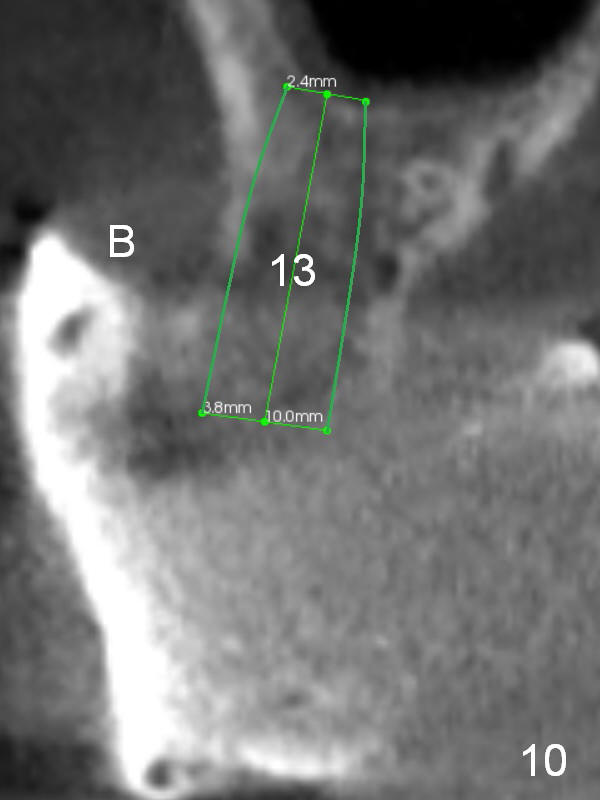

Implant placement will be divided into 2 stages for each arch. In the 1st one, implants will be placed at #3 and 11-13; the 2nd one, at #5, 6, 8 and 9. After the 1st implant placement, the upper denture will be retained by ball abutments and soft relined (pushed posteriorly). Two or 3 months later, four more implants are placed and a new provisional (pepper & salt technique) are supported by cemented abutments and implants.

The maxillary bone is soft. Ridge split (at #5/6, and 11-13 (ridge split wheel kit) and bone expansion (bone expander kit and osteotomes) are expected. The site of #3 is wide and short and an extra wide implant is placed with sinus lift (Fig.2 (coronal CT section)).